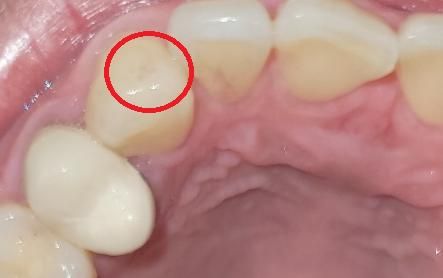

왼쪽에 있는 치아는 신경 치료하고 때운곳이고

빨간원 안에 있는 검은색 거미줄처럼 생긴게

충치처럼 보이기도 하고 혈관이 터진것처럼 보이는데요

혹시 충치일까요?

치아에 착색이 된거 같습니다. 치과에 가셔서 스켈링 및 착색제거를 받으시면될것같습니다.

사진으로는 정확한 확인이 어려워 보입니다. 단순한 착색일 수 있습니다. 단순한 착색일 경우에는 간단하게 치과에서 제거할 수 있으니 자세한 확인을 위해서 치과에서 진료를 받아보는 것이 좋습니다.

해당부위는 혈관이 지나가진 않고요 충치의 양상도 아닙니다 얼룩이 그렇게 생기는게 흔한건 아닌데 일단 얼룩, 착색일지 스케일링 통해 제거해보시기 바랍니다